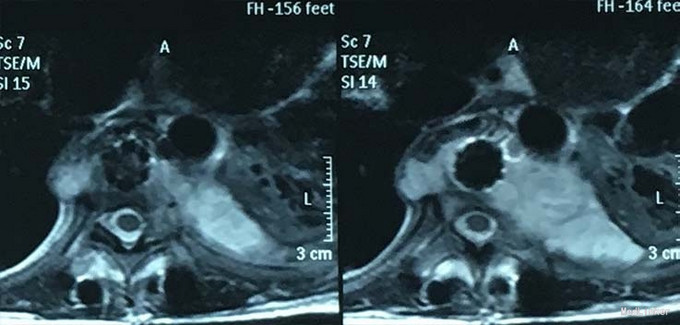

查体:脊柱外观无明显畸形,颈椎活动度正常,胸背部可见纵向长约15cm切口,皮肤钉缝合,伤口愈合可,无红肿渗液。胸椎9-10体左侧棘突旁局部压痛(+)、叩击痛(-),压头试验阴性,双侧侧臂丛牵拉实验(-),双上肢肌张力、运动、感觉及反射无明显异常、躯体感觉无明显减退,双下肢髂腰肌、股四头肌、胫前肌肌力IV级,感觉正常,双下肢直腿抬高试验(-),双侧腱反射对称略活跃,双侧Hoffman征(-),双侧Babinski征(-),双侧髌阵挛(-),踝阵挛(-)。 辅助检查:2015-11外院胸椎MRI检查发现T9-10节段椎体肿瘤并椎旁软组织肿块形成,肿块突入胸腔占位

诊断:胸椎椎体肿瘤(T9-10) 治疗:先于外院行1期后路椎弓根钉固定融合手术,然后转入我院行介入下术前椎体节段血管栓塞手术,第二天行经左侧胸腔入路椎体肿瘤病灶刮除并钛网植骨植入重建手术。术后恢复满意。复查MRI显示肿瘤病灶基本完全切除。